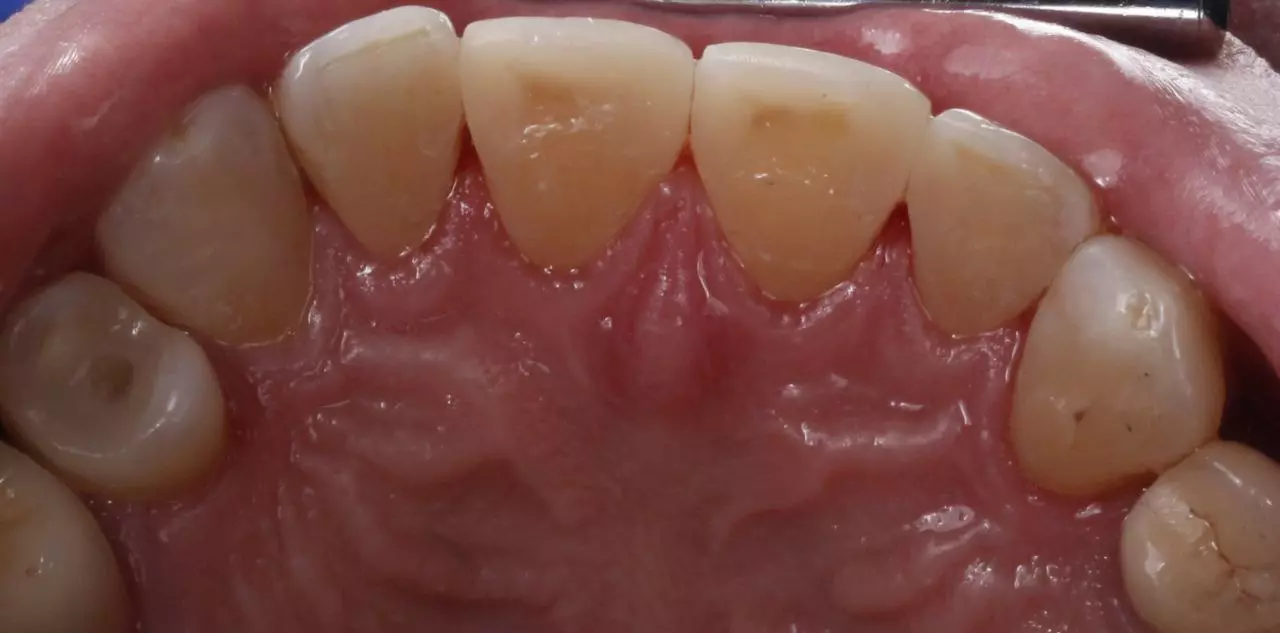

Лікування карієсу

Лікування карієсу 41, вторинного карієсу 31.